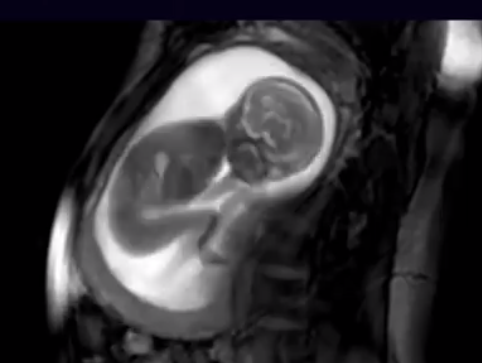

Pamje e rrallë e lëvizjes së bebes në trupin e nënës (Video)

Mbajtja e një fëmije në bark përillet me "trazira" herë më të mëdha e herë më të vogla, por përfundimisht, këto trazira nuk janë...